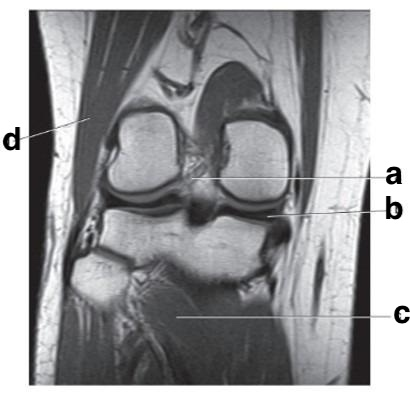

Medial meniscus

posterior cruciate ligament

medial collateral ligament